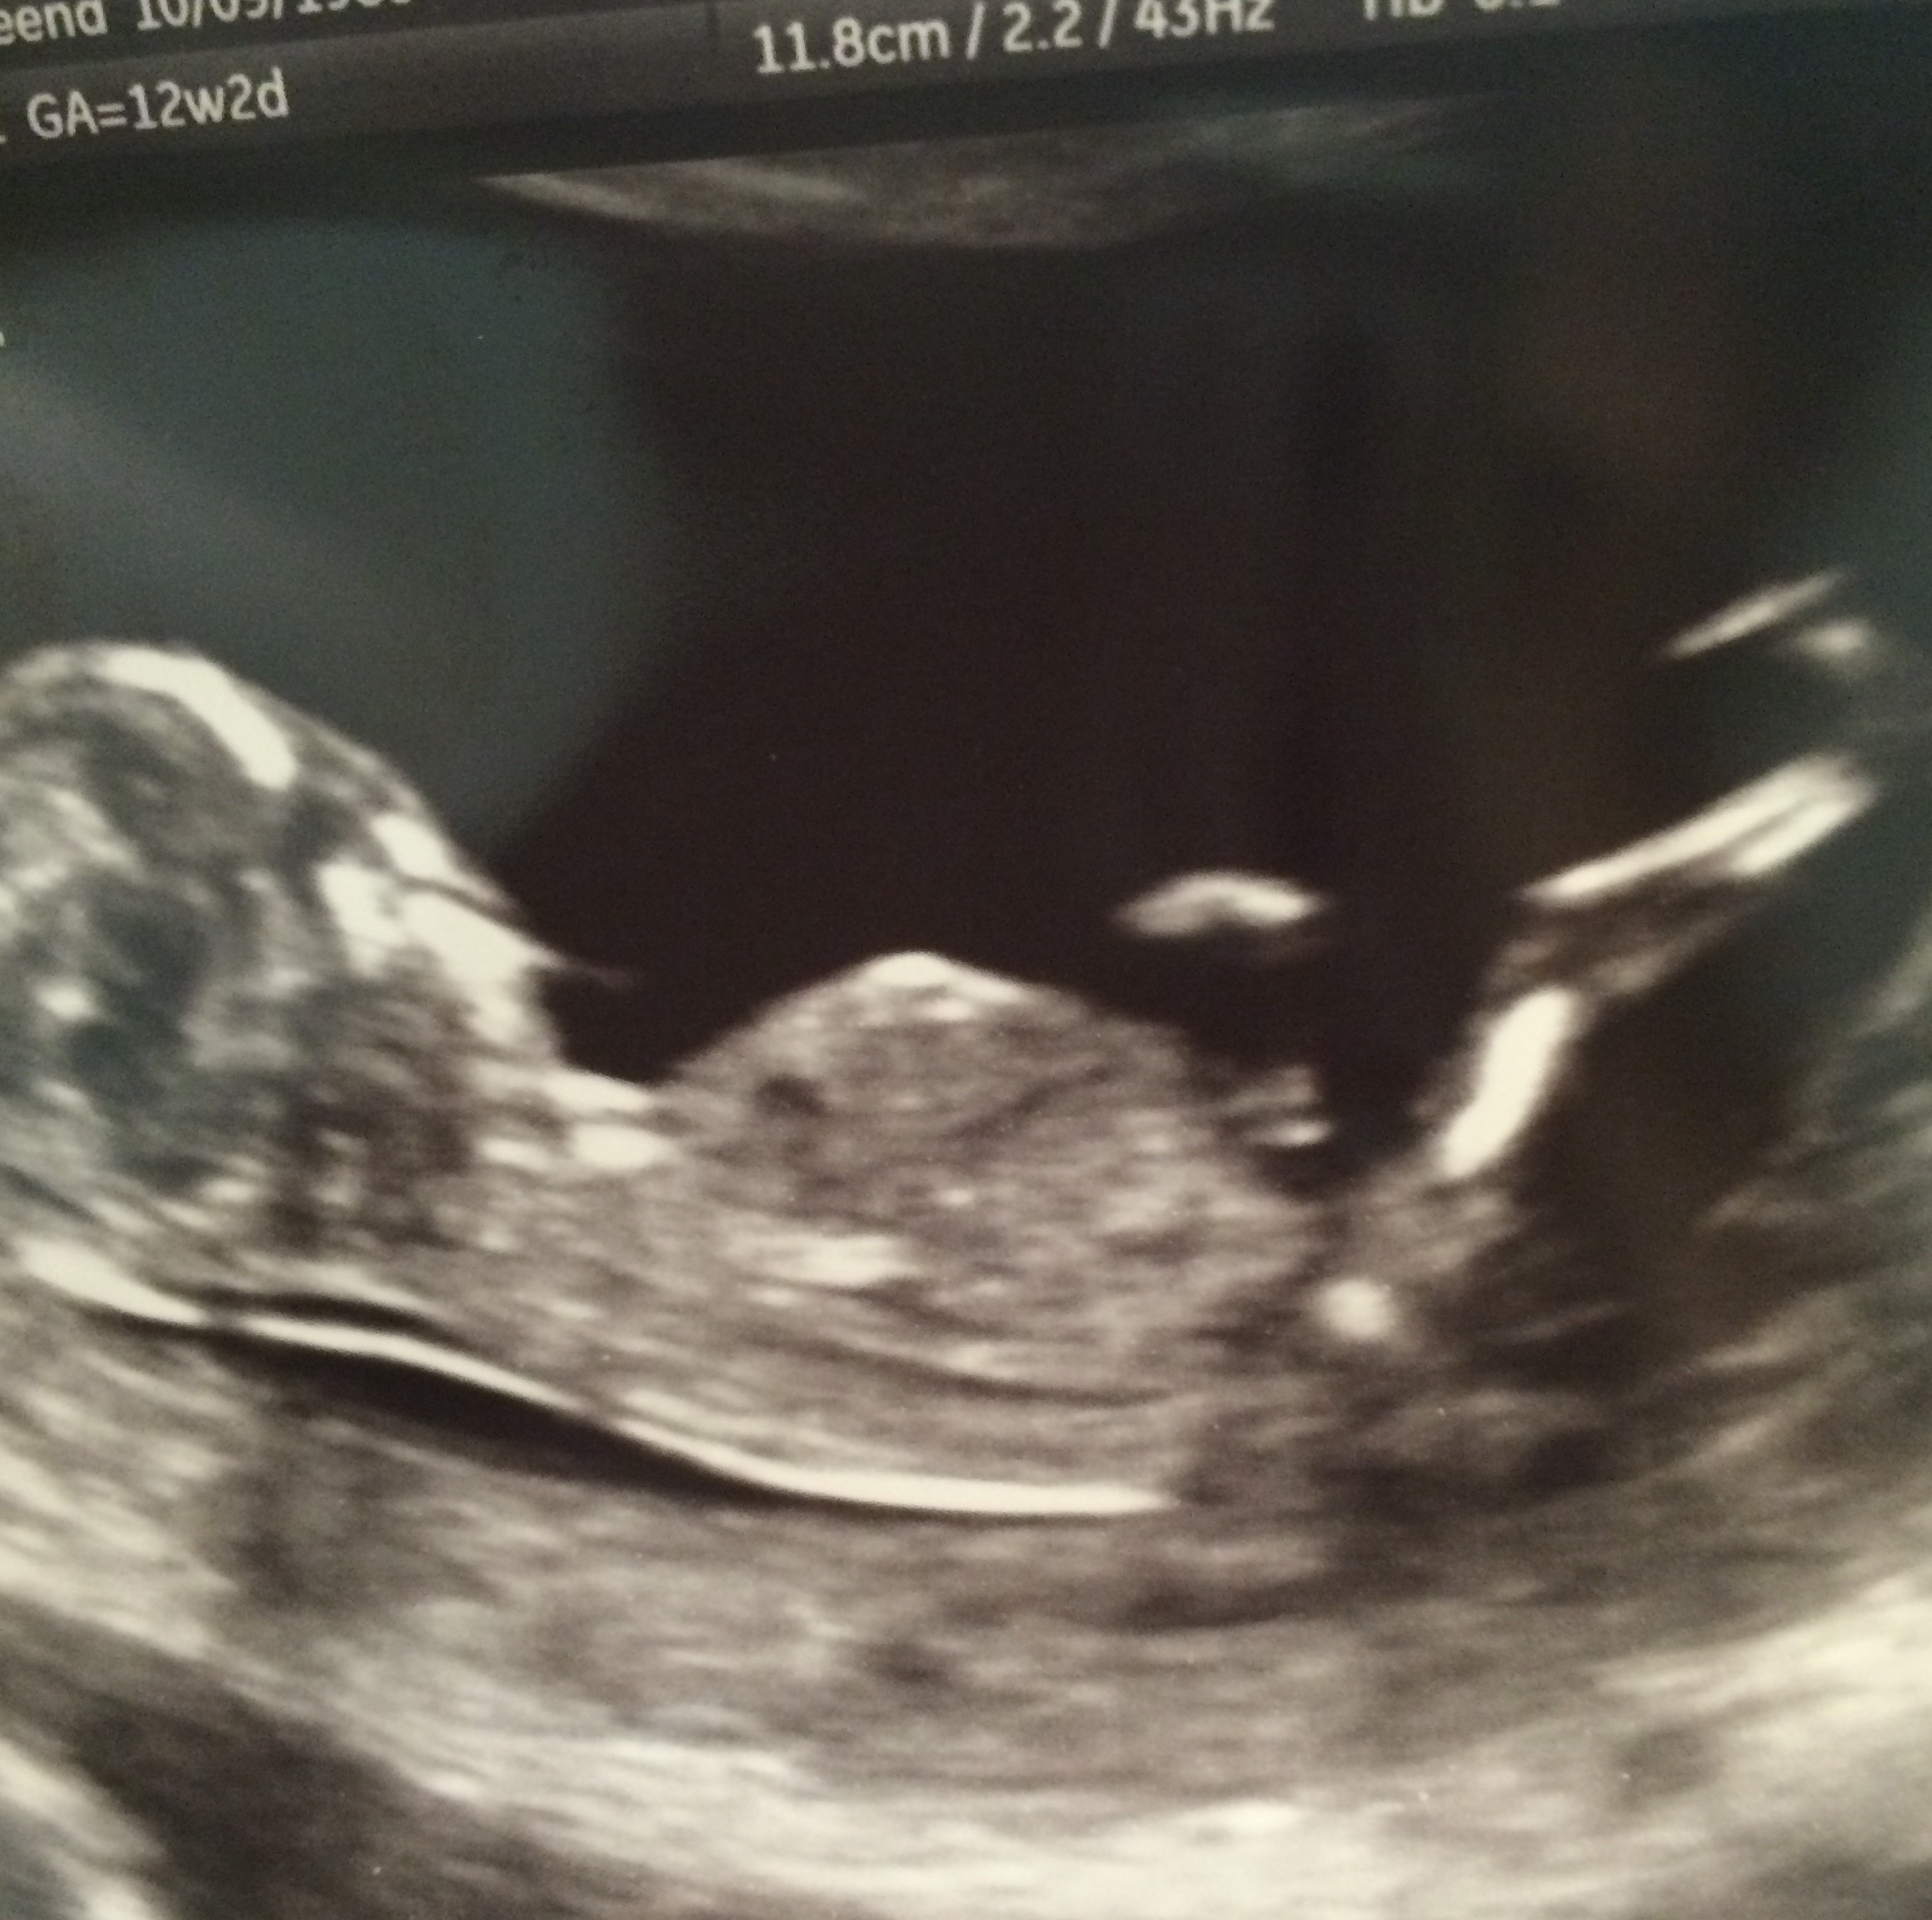

We had our NT scan today and we got some good views but I really need some input on what you think our baby is. I am 12 weeks 2 days pregnant and baby is measuring a few days larger. Thank you so much in advance for looking and guessing! ❤️

I think I would give a slight boy lean as I think I may see some stacking on that nub.

My first thought was boy.